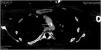

A 40-year-old woman with no relevant medical history was admitted to the ICU due to cardiogenic shock with severe systolic dysfunction and generalized hypocontractility evidenced by transthoracic echocardiography (TTE). Invasive monitoring was attempted using a thermodilution system, with great difficulty in securing ultrasound-guided access to both femoral arteries. A significant pressure gradient between the upper and lower extremities was observed. With a strong suspicion of aortic disease, a guided CT angiography study was requested, which revealed an extensive calcified atheroma plaque in the aortic arch (Fig. 1), with important obstruction in the sagittal plane reconstruction (Fig. 2). Repeat TTE was performed due to the strong suspicion of coarctation, recording a maximum systolic gradient in the descending thoracic aorta of 89 mmHg, which confirmed the disorder (Fig. 3). An endovascular approach was adopted to place a thoracic endoprosthesis supported by an intra-prosthetic steel stent. The subsequent course proved favorable, with a gradual return of ventricular function to normal levels, leaving a residual gradient of 32 mmHg.